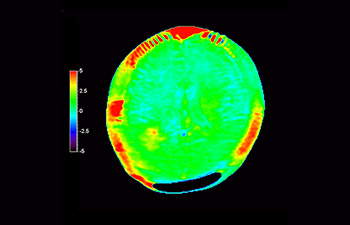

3D APT (Amide Proton Transfer) is a unique, contrast-free, brain MR imaging method addressing the need for more confident diagnosis in neuro oncology. 3D APT uses the presence of endogenous cellular proteins, to produce an MR signal that directly correlates with cell proliferation, a marker of tumoral activity. 3D APT can support trained medical professionals in differentiating low grade from high grade gliomas and, in differentiating tumor progression from treatment effect1.

3D T1w TFE 3D APT

Astrocytoma 3d apt

Brain astrocytoma, post-radiotherapy

with 3D APT